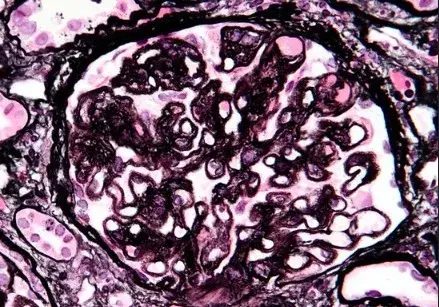

Nefropatia Membranosa: e se o paciente não responder ao tratamento inicial?

Nefropatia Membranosa: e se o paciente não responder ao tratamento inicial?

Como fazer o tratamento da Nefropatia Membranosa de forma prática!

Como fazer o tratamento da Nefropatia Membranosa de forma prática!